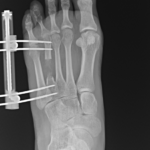

The actual lengthening or straightening of the limb begins 1-2 weeks after surgery. At that time, adjustments are made to the apparatus usually four times a day. Detailed instructions are provided to the patient to ensure they fully understand what is required.

The bone ends are separated at a rate of 1 mm per day.

During the adjustment phase, the patient is followed up in the rooms every two weeks with clinical examination and x-rays. Close scrutiny is maintained to identify any complications early.

Distraction phase– 1mm/day until the desired length is achieved.